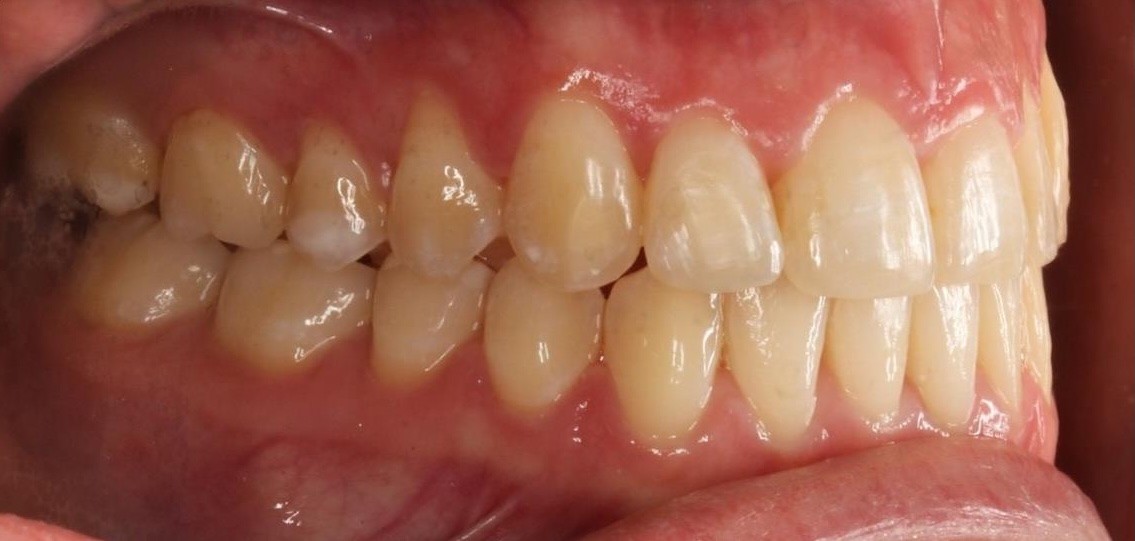

Diganosis: Moderate crowding in both arches, constricted arch forms with anterior and posterior single tooth crossbites, poor smile display

Final results

INTRAORAL